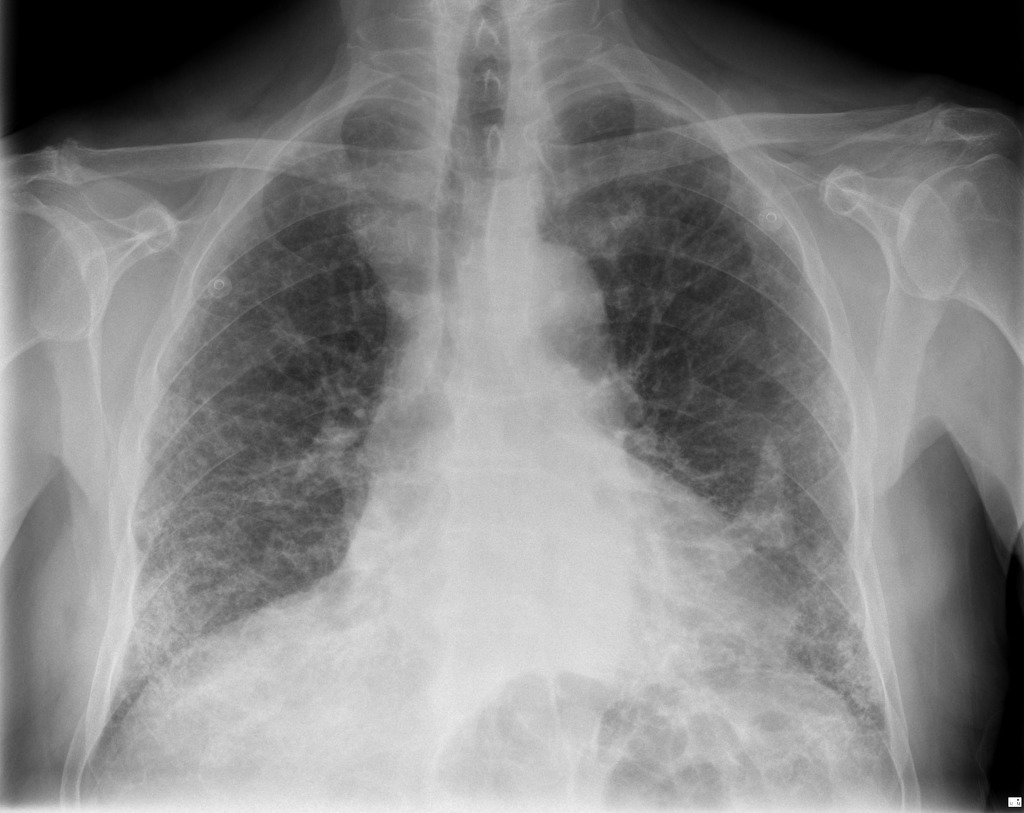

Por desgracia, el problema con el uso del amianto es que es muy peligroso y puede dañar seriamente la salud de aquellos que se exponen a él. Ya en el siglo I después de Cristo muchos de los esclavos que se dedicaban al tejido del amianto morían de manera prematura. Y a esto se sumaron multitud de problemas que, tiempo después, se vincularon al cáncer.